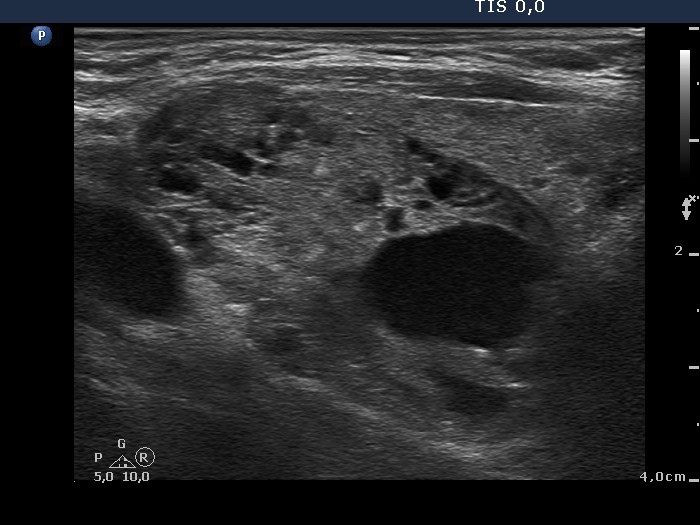

Benign hyperplastic nodule (histological diagnosis) - case 653

Note the linear figures in the back wall of the cystic areas. The ventral solid area of the nodules contains both hyperechogenic lines and granules; therefore these figures correspond to connective tissue. It is ambiguous whether the echogenic figures in the dorsal solid area (right image) are presentations of connective tissue or posterior acoustic enhancements but the former seems to be more likely.